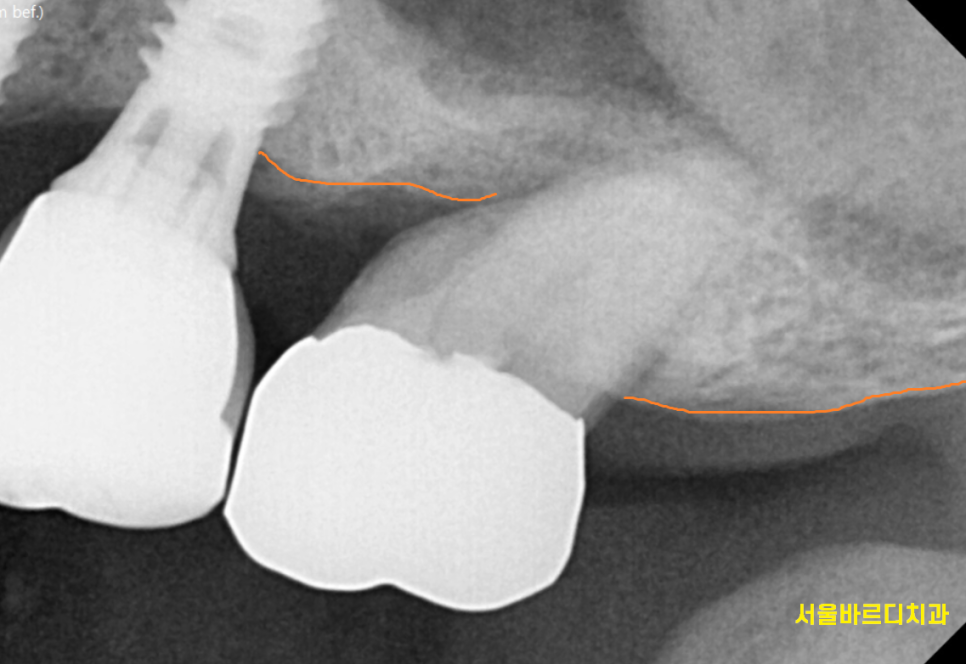

24.03.29

내원하셨을 때는

잇몸 풍선 터져서 오셨는데요.

여전히 고름이 나오고

좋지 않은 상황이었습니다.

신경치료도 되어있고

뼈도 많이 녹아있어서

발치 후 미사역 임플란트 하기로

상담해드렸습니다.